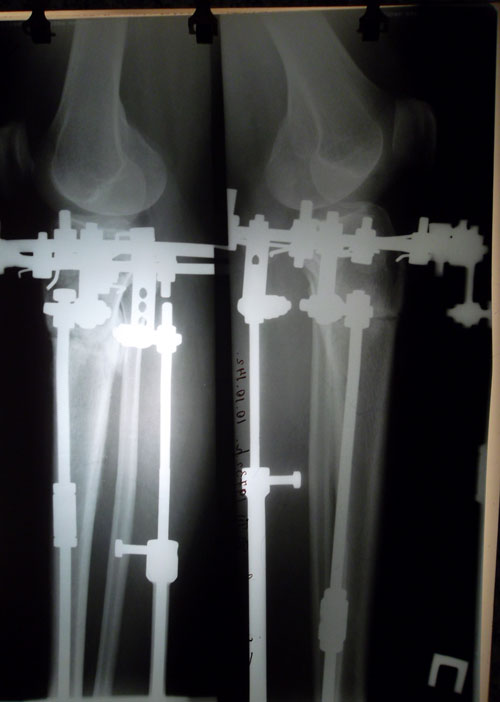

Дата операции 01.07.2014г.

Дата снятия аппаратов 17.10.2014г.

Срок лечения 97 дней.

Ооооо,мои поздравления!Наконецто сняли!теперь будьте осторожны,кости еще слабые ,ну в общем неплохо получился результат!я потеряла ваш номер,это я Жансая!Боже когда у меня будут идеальные ноги?Уффф!